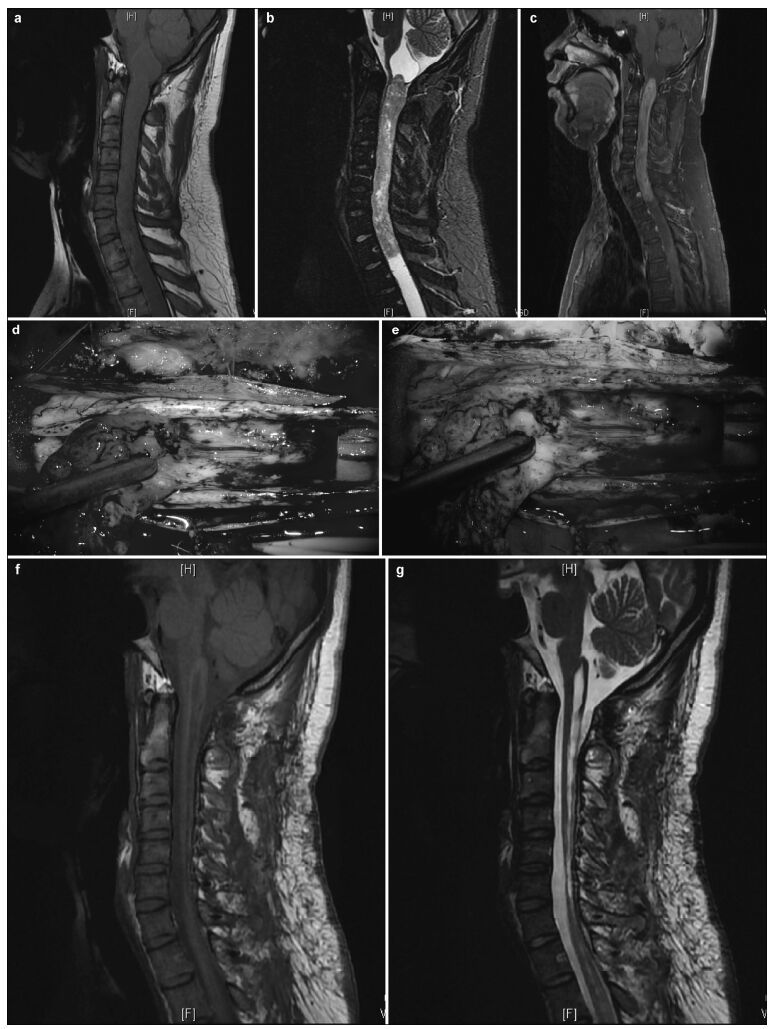

| Figure 3 Intramedullary ependymomas at C3-C7, and tumor-associated stroke. (a) Preoperative T1 image showing spinal cord thickening and cysts in the septum. (b) Preoperative T2 image of a mass at C3-C7 and cysts in the septum. Stroke was not detected. (c) Preoperative enhanced magnetic resonance image showing an intramedullary tumor as a distinctive mass at C3-C7. Stroke enhancement was undetected. (d) Indistinct tumor images, intraoperatively, under fluorescent illumination. (e) Distinct intraoperative image of a tumor under the microscope. (f) Intraoperative and 1-month postoperative T1 images show the absence of tumor residuals or relapses. (g) T2 images, 1 month after surgery, show the absence of tumor residuals and relapses. |

3 Results 3.1 Intraoperative tumor statusIn the absence of FS, 80 patients demonstrated clear tumor boundaries and 32 had blurry tumor boundaries resulting from tumor adhesion to the spinal cord, including 14 with severe adhesions and intramedullary tumor-associated strokes (Figures 1-3). Under fluorescence, tumors were visible in 94 patients and invisible or indistinct in 18, including 14 with intramedullary tumor-associated strokes and indistinct MRI enhancement and four without MRI enhancement. Under fluorescence, complete tumor removal was accomplished in 92% (103/112) of the patients. Of the nine patients with tumors that could not be completely removed, five had myxopapillary ependymomas at the conus medullaris and four also had strokes and severe adhesions.

3.3 Comparison of imaging and intraoperative fluorescence findingsOf the 112 cases, 94 (83.9%) had enhanced preoperative MRIs and distinct intraoperative fluorescent images, four had indistinct MRI enhancements and fluorescent images during surgery, and 14 had tumor-associated strokes associated with non-uniform MRI enhancement and indistinct fluorescent imaging, intraoperatively (Figure 3). The present study included 90 patients with combined syringomyelia, 88 of whom did not present with cyst wall enhancement during either their preoperative MRI examinations or with intraoperative fluorescent cyst walls, and one who presented with preoperative cyst wall MRI enhancement and intraoperative fluorescent cyst wall images.

For patients with tumor-associated stokes, white light is required intraoperatively to detect and remove the tumors. However, hemosiderin deposits can cause tumor cells to tightly adhere to normal spinal cords, increasing the difficulty of assessing tumor boundaries and residuals under both white light and fluorescent illumination. Hyperplasia of small blood vessels increases the blood supply to tumors, which also makes surgery more difficult. In the present study, one patient presented with cysts at both ends of the tumor (determined using MRI) and at the cyst wall (evidenced using intraoperative fluorescent imaging), indicating possible tumor cell infiltration and metastasis.